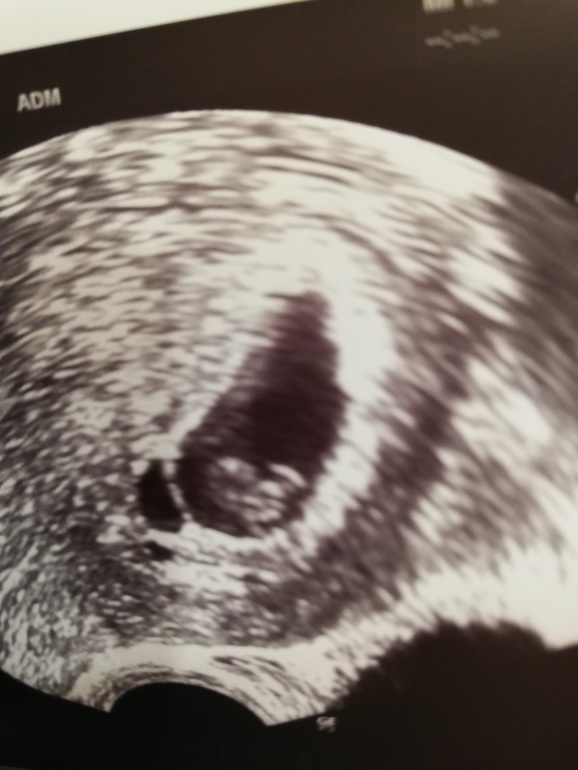

Плодное яйцо с "кладовкой"

Анализы и процедуры. Помощь в расшифровке результатовДевочки, привет. Мне подсаживали одну бластоциту 7 октября. Только что с узи, увидели эмбрион, но врачу не очень понравилось моё плодное яйцо. Оно похоже на печень 😂 есть основная часть, а есть как отросток рядом.

Вот думаем, либо эмбрион разделился, а второй не прижился, либо это просто складка. Но откуда она? Было у вас что-то подобное?

вот он!